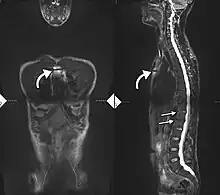

Imaging

X-rays

The earliest changes demonstrable by plain X-ray shows erosions and sclerosis in sacroiliac joints. Progression of the erosions leads to widening of the joint space and bony sclerosis. X-ray spine can reveal squaring of vertebrae with bony spur formation called syndesmophyte. This causes the bamboo spine appearance. A drawback of X-ray diagnosis is the signs and symptoms of AS have usually been established as long as 7–10 years prior to X-ray-evident changes occurring on a plain film X-ray, which means a delay of as long as 10 years before adequate therapies can be introduced.[26]

Options for earlier diagnosis are tomography and MRI of the sacroiliac joints, but the reliability of these tests is still unclear.

T1-weighted MRI with fat suppression after administration of gadolinium contrast showing sacroiliitis in a person with ankylosing spondylitis